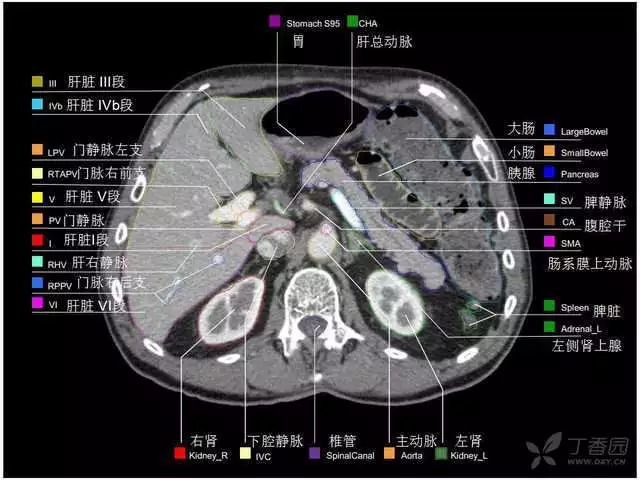

腹部肝脏高清CT断层的图谱

全腹部高清CT图谱,淋巴结彩色图谱,血管解剖图谱大汇总!

肝段,肝内管道的分布规律

美国放射学会ACR官网,对肝脏的区域和节段解剖学概述